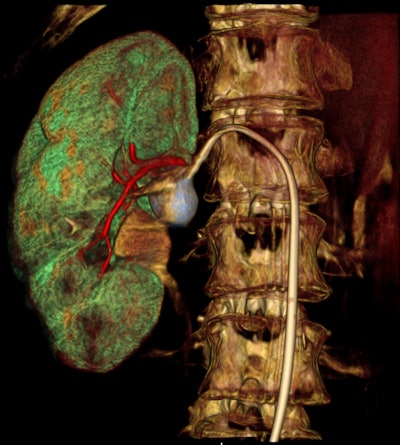

As interventional procedures become more complex, advanced 3D acquisition is becoming increasingly important, he pointed out. There is also an emphasis on flexible, responsive technology, so the C-arm's lateral movement allows it to be moved out of the way during a procedure. During lung biopsies, for example, the unit can be flipped through 180ï‚° to place the flat-panel detector beneath the patient table.